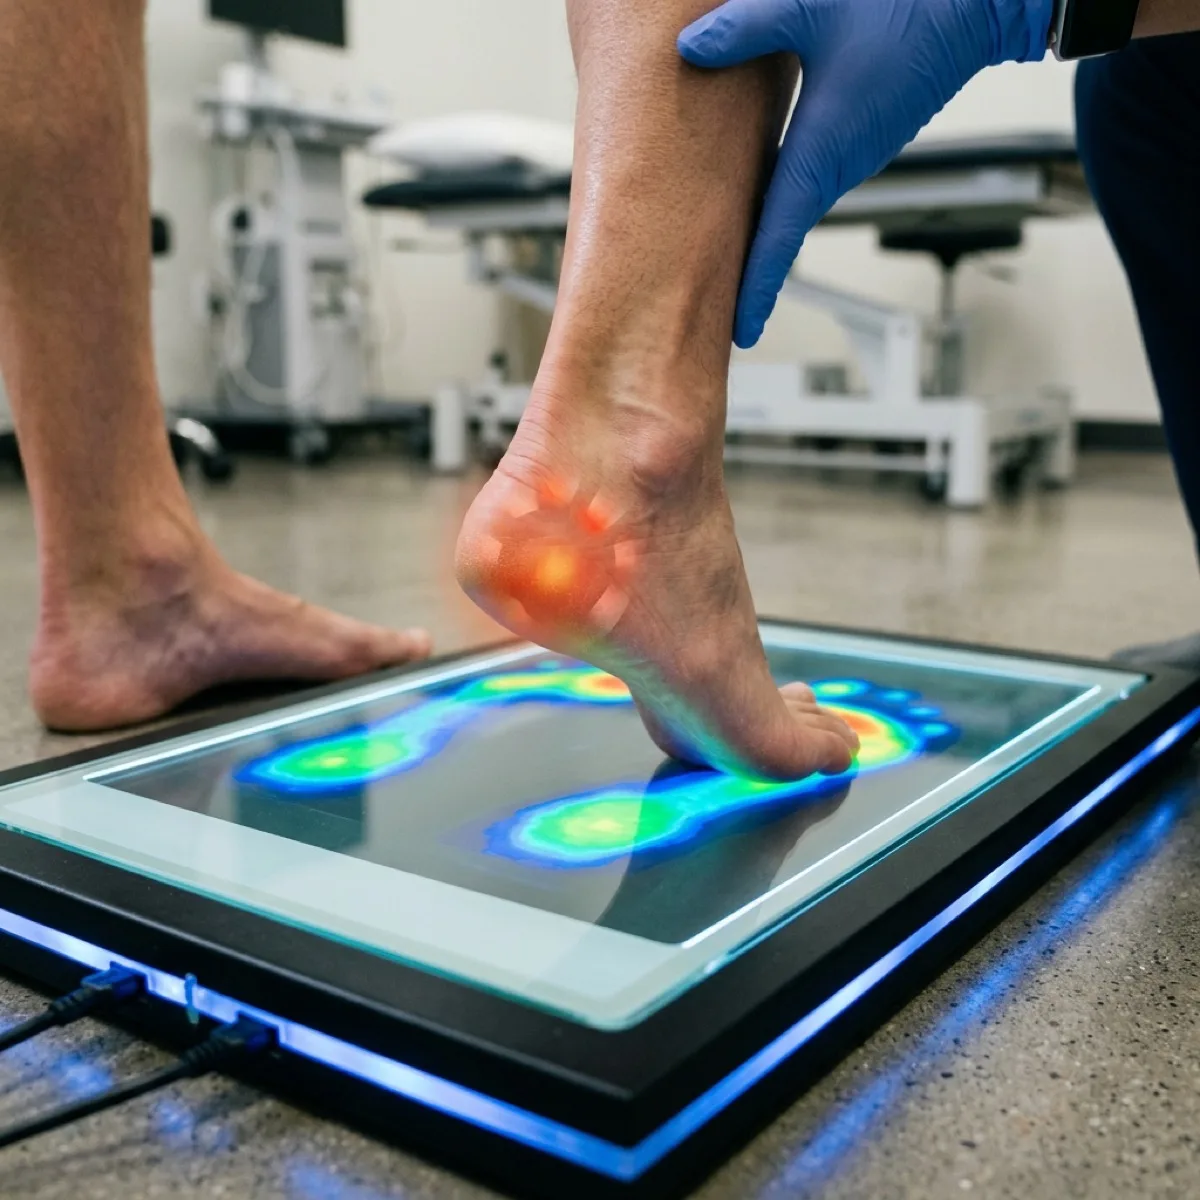

El estudio baropodométrico es el examen más completo para entender cómo pisas. Te explicamos en qué consiste, cómo se hace y cómo puede cambiar tu calidad de vida.

La biomecánica de la marcha estudia cómo caminas y cómo cada paso impacta tu cuerpo. Descubre por qué un análisis de marcha puede resolver dolores que llevas años soportando.